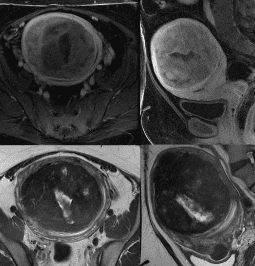

자궁근종은 어떻게 진단하나요?

자궁근종은 골반 진찰과 초음파 검사로 진단할 수 있습니다. 점막하 자궁근종의 경우에는 초음파 자궁조영술이 필요할 수 있습니다